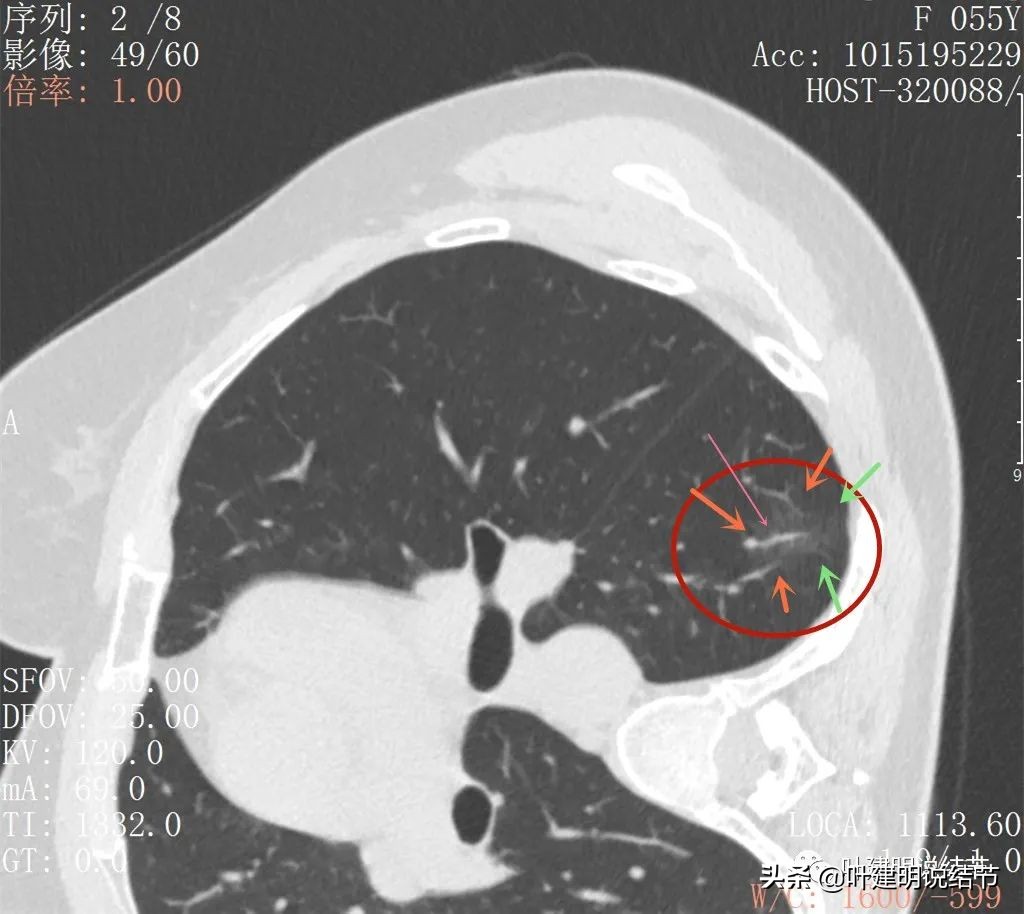

上图见多支血管走向病灶(桔色箭头)灶内有异常增粗血管穿行(细粉色箭头),病灶明显有磨玻璃成分,只是比较淡(绿色箭头)

病灶处有多支血管聚集的味道

边缘区密度更低的磨玻璃成分